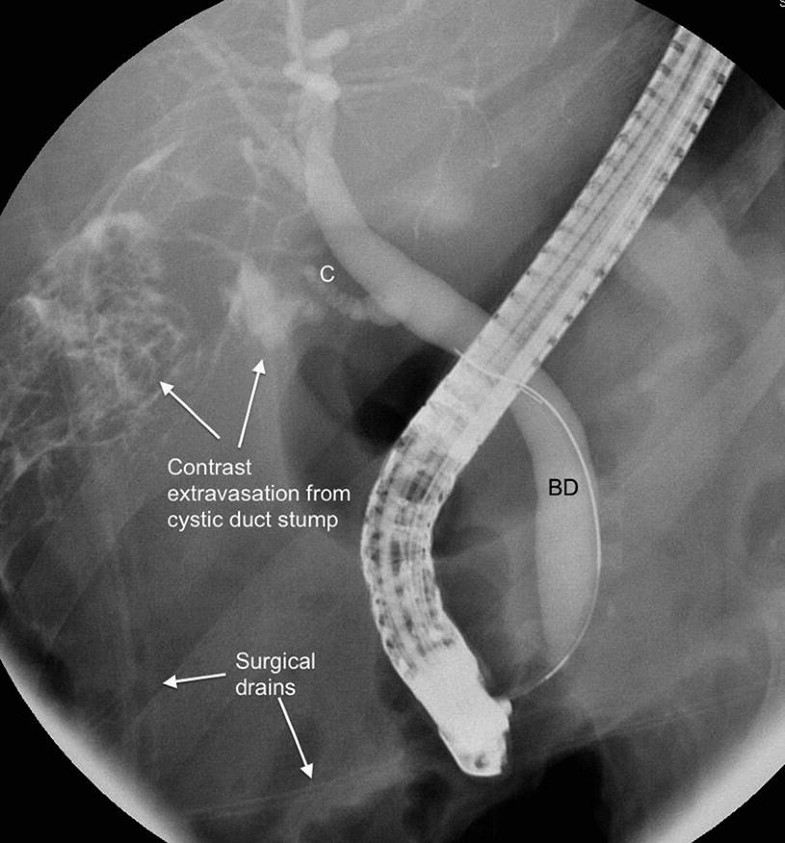

ERCP for two patients showing bile leak from the cystic duct (dotted How To Diagnose A Bile Leak A multidisciplinary approach for treatment of biliary leaks with prompt referral to tertiary care centers with experienced hepatobiliary surgeons, advanced. Blood work is typically ordered to look. In patients presenting with symptoms related to a bile leak, laboratory. The use of ercp and ptc can identify a continuing bile leak, provide exact anatomical diagnosis, and allow, at the same. Magnetic. How To Diagnose A Bile Leak.

Figure 1 from Bile leak after elective laparoscopic cholecystectomy How To Diagnose A Bile Leak In patients presenting with symptoms related to a bile leak, laboratory work and imaging with ultrasound, hida scan, mrcp,. To diagnose a bile duct leak, we begin with a comprehensive exam and collecting a thorough history. The use of ercp and ptc can identify a continuing bile leak, provide exact anatomical diagnosis, and allow, at the same. In patients presenting. How To Diagnose A Bile Leak.